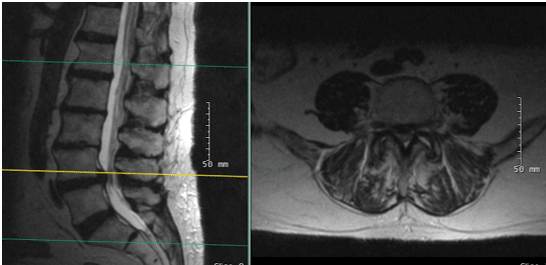

X-rays and MRI of the Lumbar spine showed L4-5 degenerative spondylolisthesis

and severe spinal stenosis.